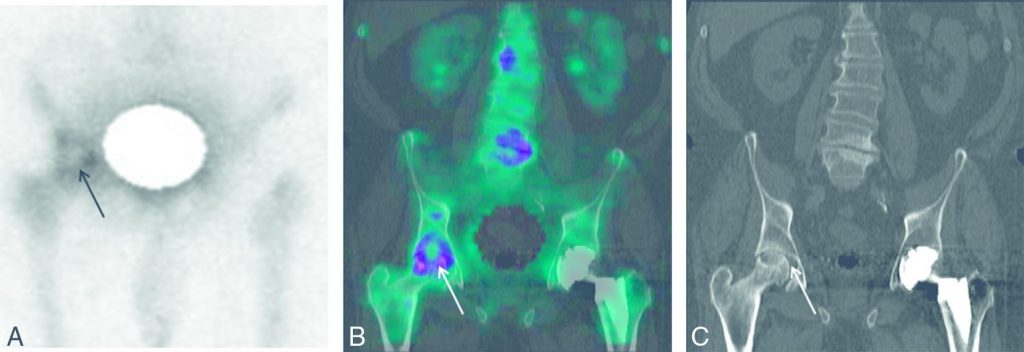

Fig. 85.5 Ostéonécrose de la tête fémorale droite.

Scintigraphie osseuse : hyperfixation en « cocarde » de la tête fémorale droite sur les images TEMP (A), TEMP-TDM (B) en coupes coronales correspondant à une image en « coquille d’œuf » sur l’image TDM (C).

Source : CERF, CNEBMN, 2022.